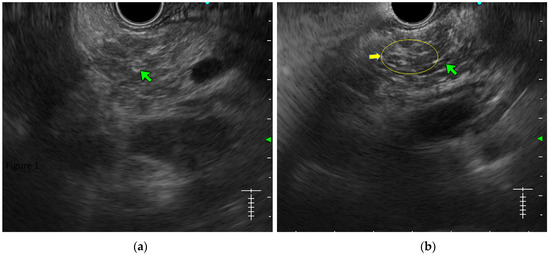

- Lobularity with and without honeycombing: Lobules are described as well-circumscribed reticulated areas ≥5 mm in size, with a relatively hyperechoic rim compared to the adjacent central area. When these lobules are non-contiguous, the EUS pattern is described as ‘lobularity without honeycombing’. When at least three of such lobules are contiguously located in the body or tail region, the pattern is defined as ‘lobularity with honeycombing’ in EUS [30,31]. (Figure 2) The exact histopathological correlation of lobularity is not precisely known. Studies, however, have demonstrated lobularity to correlate with increased fat and collagen in biopsy specimens, and in a recent study, lobularity was demonstrated to be associated with increased disease severity, a higher level of inflammation, and a trend towards a higher grade of fibrosis and atrophy compared to the absence of lobularity in EUS [32,33];

- Hyperechoic margin of the MPD: It is described when the hyperechoic ductal wall over at least 50% of the MPD is demonstrated in the body and the tail of the pancreas. In a linear echoendoscope, MPD assessment on a long axis is difficult. Thus, this finding is often subjective and has low interobserver agreement [34]. Histologically, they correspond to periductal fibrosis. In the study by Sekine et al., the hyperechoic MPD wall was described to correlate with the thinning of the ductal wall on surgical specimens [33] (Figure 2).